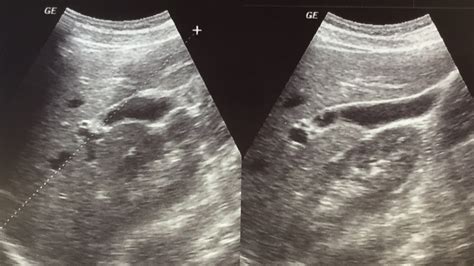

Undergoing a medical imaging procedure can often feel overwhelming, especially when you are unsure about what to expect. If your doctor has ordered an imaging scan of your abdomen, you might find yourself searching for the right Liver Ultrasound Prep instructions to ensure your results are accurate. A liver ultrasound is a non-invasive, painless diagnostic tool used to examine the size, shape, and health of your liver, as well as the surrounding structures like the gallbladder and bile ducts. Because the digestive system produces gas, and the liver sits deep within the abdominal cavity, specific preparation is required to provide the sonographer with a clear "window" to capture high-quality images.

Once you arrive at the imaging center having completed your Liver Ultrasound Prep, the procedure is quite straightforward. You will typically be asked to lie on an examination table, usually on your back or slightly on your side. The sonographer will apply a warm, water-based gel to your upper abdomen. This gel is essential as it eliminates air pockets between the skin and the transducer, allowing the ultrasound waves to travel directly into your body.

The sonographer will then move the handheld transducer firmly across your skin. You might be asked to change positions or take deep breaths and hold them; this helps move the liver slightly, allowing the technician to capture images from different angles. The entire process is painless and generally lasts between 30 to 45 minutes.